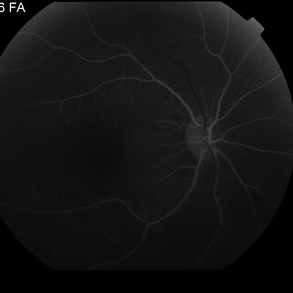

Proliferative Diabetic Retinopathy with Vitreous Hemorrhage - FA early

Oct 18 2012 by Suber S. Huang, MD, MBA, FASRS

30 year old diabetic man with proliferative diabetic retinopathy and vitreous hemorrhage

Photographer: Stacie Hrvatin

Condition/keywords: cotton wool spots, neovascularization (NV), subhyaloid hemorrhage, vitreous hemorrhage